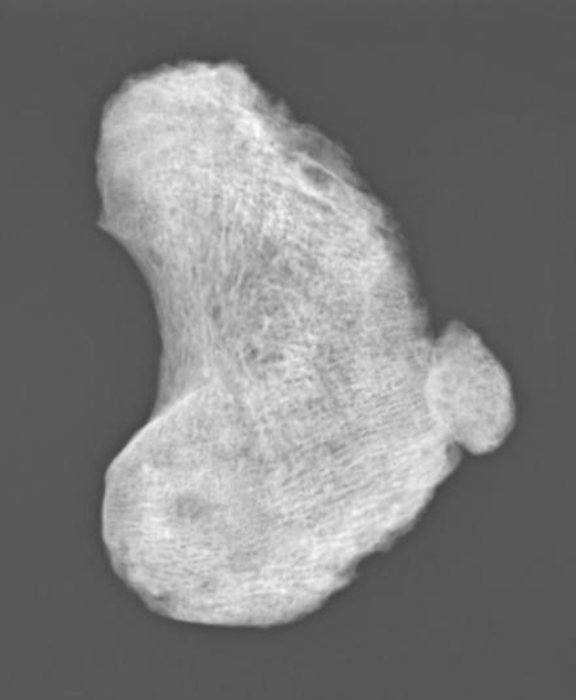

“The skeleton of the young boy (~6 years old) showed signs of disease consistent with bacterial septic arthritis, a progressive destruction of joints, probably caused by a prolonged and untreated Hib infection, which could have led to physical impairment and in the case of an additional meningeal infection also neurological impairment,” said Guellil, the Research Fellow of Ancient DNA.